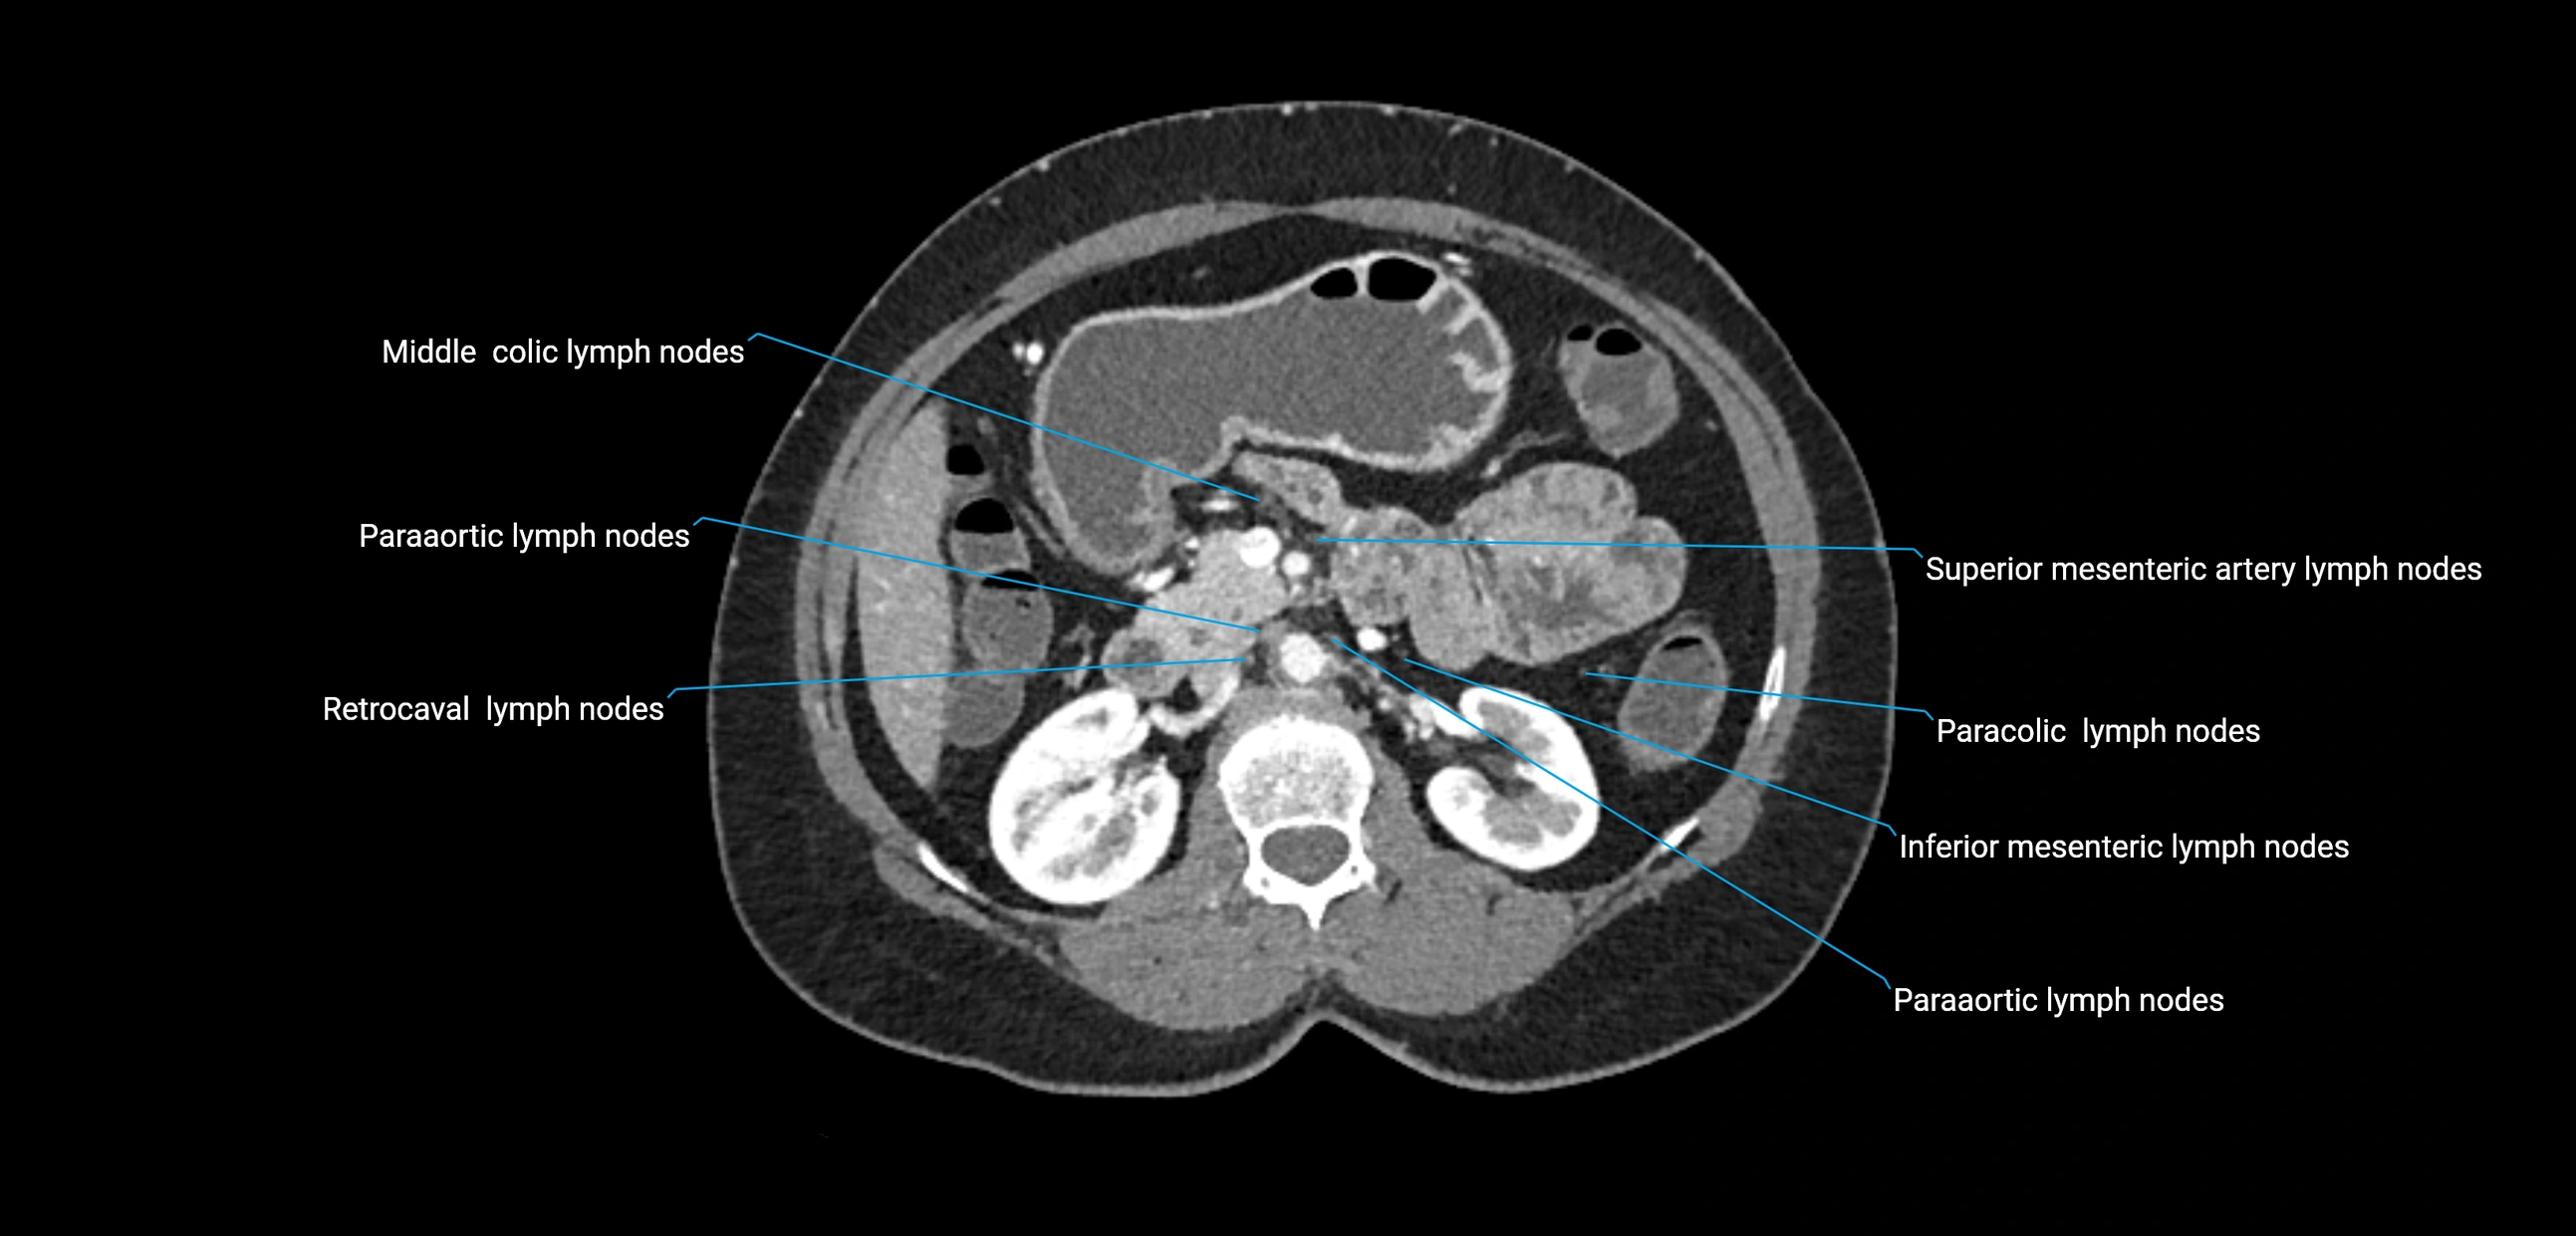

CT Appearance

CT Pre-Contrast:

• Nodes appear as soft-tissue density nodules adjacent to the aorta and IVC

• Calcification may be seen in chronic infections (e.g., tuberculosis)

CT Post-Contrast:

• Normal nodes enhance homogeneously

• Malignant nodes may show heterogeneous enhancement, central necrosis, or conglomerate formation

• Size >1 cm short axis is suspicious, though morphology and distribution are equally important

CT Venography (CTV):

• Demonstrates nodal encasement or compression of adjacent vessels (aorta, IVC, renal veins)

• Useful in staging testicular and ovarian malignancies

• Provides 3D reconstructions for retroperitoneal lymph node dissection planning